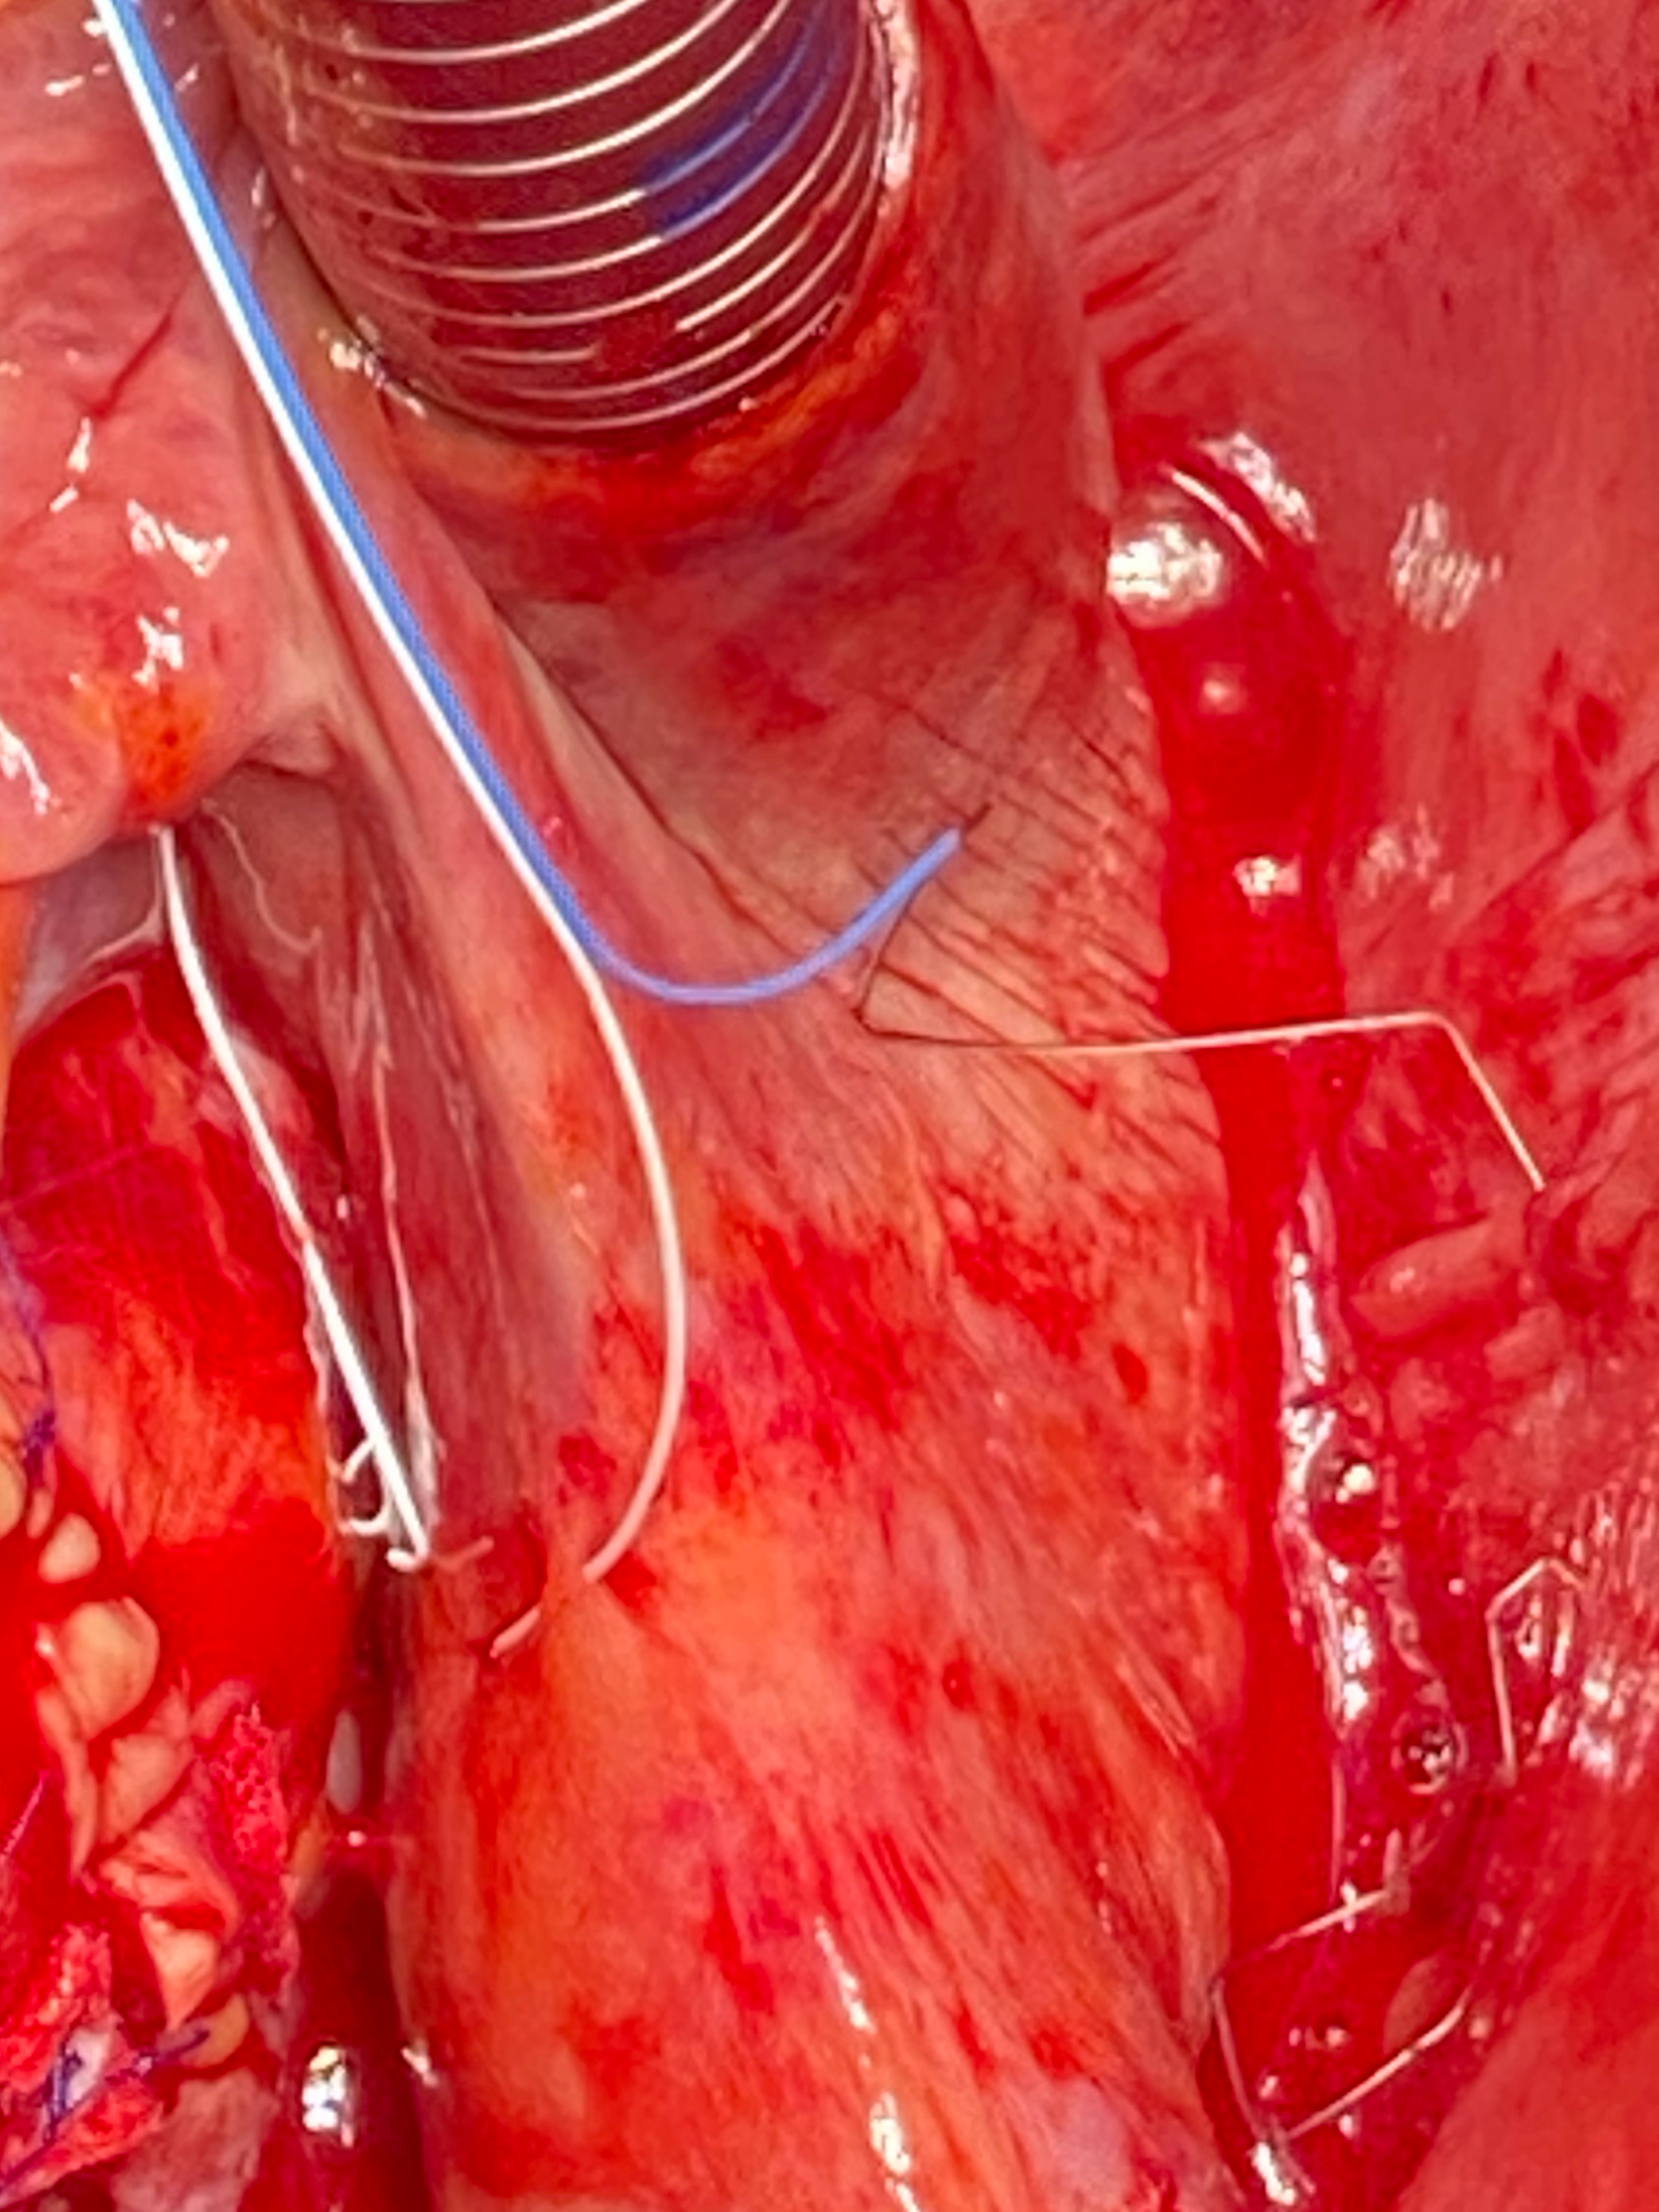

anode of the TMA® wire to the right atrium was placed and fixated

to the free right atrial wall between the superior and inferior vena cava (Fig. 4); and the cathode was placed at the sinus node one to two cm distal to the

anode. The electrodes were placed and stitched with meticulous care at the atria,

and guided carefully in the pericardium to ensure smooth extraction. Special

attention was given to bypass grafts to prevent damage during extraction. The

Fig. 4.Implantation of the atrial TMA® electrodes with needles: placement of the right wire with anode stitched to the pericardium and the cathode on the superior vena cava.